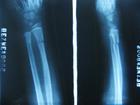

♥尺桡骨骨干双骨折

尺桡骨骨干双骨折,在前臂骨折中仅次于桡骨远端骨折而居第2位,且治疗较为复杂,预后差,为临床上的难题之一。除注意一般骨折症状外,尚应注意有无血管,神经及肌肉组织的伴发伤,尤其是被机器绞压者,软组织的损伤可能重于骨的损伤,易引起挤压综合征或缺血性挛缩等,在临床检查时必须反复加以强调。[1]